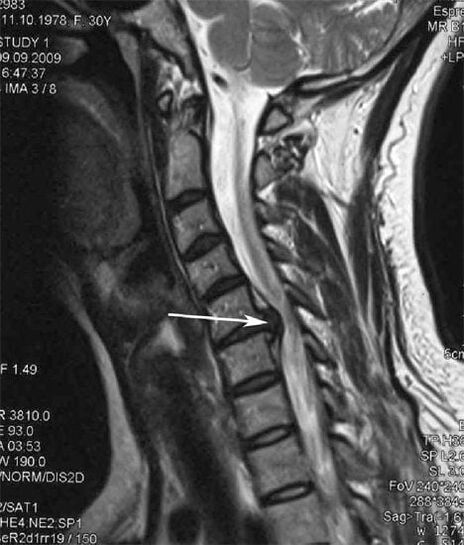

Алгачкы этаптарда мри колдонуу менен Остеофондроз аныкталды. Кийинчерээк патологияны рентгенографияны колдонуп диагнозу коюлушу мүмкүн. Моюнчанын омуртканын радиографтарында омурткалардын ортосундагы аралыкты азайып, бетине муундардагы патологиялык өзгөрүүлөрдүн жана остеофитоздун өзгөрүшү байкалууда.

Көпчүлүк адамдар өз мойнуна алдырбагандыктан, бир нерсени капысынан көтөргөндөн кийин, мойнуна бурула албай тургандыгына нааразы болушат. Бул кубулуш грнанын дискинин пайда болушун көрсөтөт. Арткы, моюн жана жогорку бут кийимдин себеби - жүлүндөн пайда болгон нерв тамырларынын бирин чыңдоо.